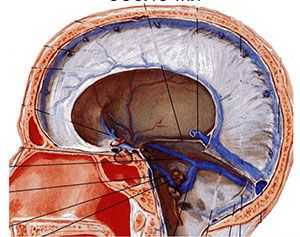

Синусы твердой оболочки головного мозга,sinus durae matris, представляют собой каналы в расщеплениях твердой мозговой оболочки, выстланные эндотелием, по которым оттекает венозная кровь от головного мозга, глазницы и глазного яблока, внутреннего уха, костей черепа и мозговых оболочек. Из синусов она попадает во внутреннюю яремную вену, которая берет начало в области яремного отверстия черепа. Кроме того, синусы участвуют в обмене спинномозговой жидкости. По своему строению они значительно отличаются от вен, на поперечном разрезе имеют треугольную форму. При разрезе синусы не спадаются, клапаны в их просвете отсутствуют. Такое строение способствует свободному оттоку крови от головного мозга, независимо от колебаний внутричерепного давления. Основные венозные синусы:

Рис. 2.18. Венозные синусы твёрдой оболочки головного мозга и их связи с vv.diploicae и наружными венами головы (схема).

1 - vv. diploicae; 2 - sinus sagittalis superior; 3 - sinus transversus et confluens sinuum; 4 - sinus sigmoideus; 5 - v. occipitalis; 6 - v. jugularis interna; 7 - v. facialis; 8 - v.angularis; 9 - sinus cavernosus; 10 - v. temporalis superficialis.